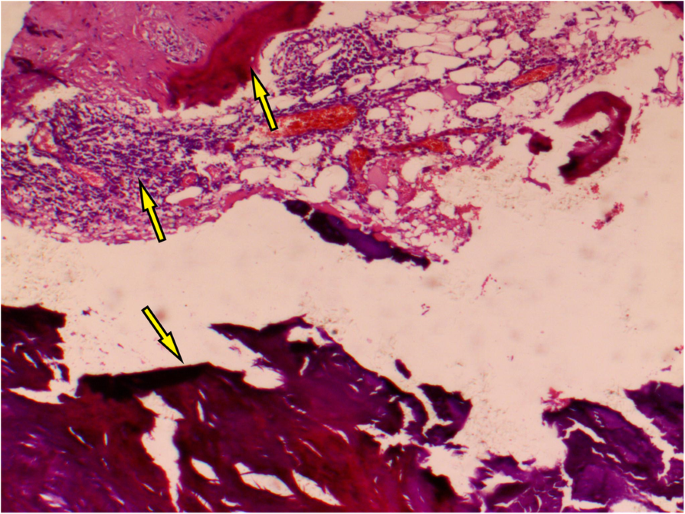

To relieve the symptoms of soreness on the right side of the lumbar region, the patient underwent surgical resection of this lesion under general anaesthesia without partial removal of the renal parenchyma. During the operation, a hard and fluctuant cystic mass measuring 11.5 × 6.9 × 5.1 cm was found on the lateral side of the right kidney, which contained approximately 400 mL of chalky white fluid (Fig. 6). Before incising the renal mass, 70 mL cystic fluid was aspirated using the syringes (Fig. 6) and tested during the operation. No cancer cells or Mycobacterium tuberculosis were found in the smear test, which excluded the possibility of tumour and tuberculous abscess and indicated that the lesion was benign. Therefore, the cystic wall was opened by incision, and chalky calcifications were found in the inner layer of the cystic wall. The cystic wall was removed, and the cyst was not connected with the renal collecting system (Fig. 7). Postoperative culture of M. tuberculosis, aerobic bacteria and anaerobic bacteria in the cystic fluid was negative. The pathological observation showed the presence of fibrosis, calcification, infiltrated inflammatory cells, ossification and bone marrow formation in the cystic wall, so the patient was diagnosed with right renal cystic TC with ossification and bone marrow formation (Figs. 8 and 9). No recurrence was detected 1 year after surgery, and the patient’s quality of life was greatly improved.

Pathologically, TC can be divided into active and inactive phases [9,10,11], which can occur simultaneously. Amorphous granular calcifications, macrophages, osteoclast-like giant cells, and chronic inflammatory cells were seen at the active stage of TC, while calcifications were surrounded by dense fibrous tissues at the inactive stage. In this case, the pathological examination showed the presence of fibrous tissues, calcium deposition and infiltrated inflammatory cells in the calcified wall around the lesion, and especially the presence of ossification and bone marrow formation in the calcified wall. Chalky cystic fluid and granular calcification is surrounded by the circular calcified wall. These characteristics were distinctly different from the calcification of the simple renal cyst wall. After consultation with the relevant pathologists, this patient was diagnosed with renal cystic TC with ossification and bone marrow formation at the inactive stage. In addition, we only performed surgical resection of the lesion in this case and did not remove part of the renal parenchyma. During the 1-year follow-up, the prognosis for the patient was quite good, and no related complications or recurrence were found. We expect that this case report can provide valuable insights into the diagnosis and treatment of similar diseases to avoid unnecessary large-scale resection and reduce harm to patients. Some types of TC can recur after surgery [2, 10], even causing greater damage to the body; consequently, long-term follow-up is required for patients presenting renal cystic TC with ossification and bone marrow formation.